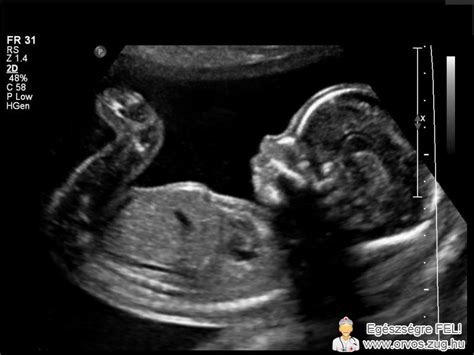

A magzat korát legpontosabban az ülőmagasság (CRL) méretével lehet kiszámítani. CRL: a fejtetőtől a farokcsontig mért hossz. A táblázatban foglalt értékeket csak támpontként szolgálnak, hogy körülbelül mikor, mekkora lehet a babád.

A magzati ultrahang méretek a 11. héttől a 40. hétig folyamatosan növekednek, tükrözve a baba fejlődését. Az ülőmagasság (CRL) a terhesség korai szakaszában a legpontosabb mutató. Később a fejátmérő (BPD), fejkörfogat (HC), haskörfogat (AC) és a combcsont hossz (FL) válik mérvadóvá a magzat méretének becslésében.